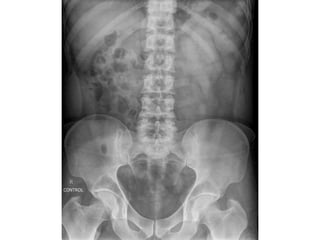

abdomen

• The most obvious finding on this CXR is free

air under the diaphragm.

• This finding indicates a bowel perforation,

unless when the patient had recent abdominal

surgery and there is still some air left in the

abdomen, which can stay there for several

days.